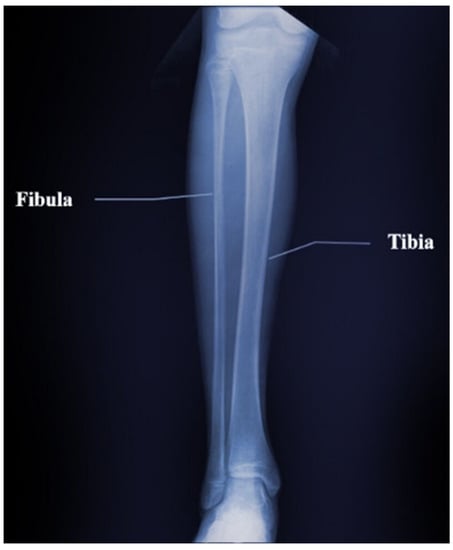

3.5. Inversion Results of the Tibia and Fibula Model

The tibia is an important bone in the calf that supports the weight of the body while the fibula is attached to the calf muscles and bears one-sixth of body weight. The two bones are connected as one by the superior tibia–fibula joint and the inferior tibia–fibula joint, and they are important bones in human BMD measurements. As shown in Figure 30, we selected a segment in the middle of the tibia–fibula pair as an objective model to better validate the extensiveness of our modified FWI algorithm. The approximate objective model is as follows:

As in Figure 31, the deep-red color represents the velocity and density of bone tissues, set at 3500 m/s and 1800 kg/m3, respectively. The blue regions represents the surrounding soft tissues of the bone, and the velocity is set at 1500 m/s, and the density is 1000 kg/m3. We present the inversion results in Figure 32. Like the previous results, our method can clearly get the good distribution of the velocity and density parameters of tibia–fibula bone pair model. There are some bad results on the left and right side of the image, because there are more cortical bone structures in the objective model, thus increasing the contrast with the surrounding soft tissue parameters and affecting the inversion results. As before, we can also expand the range of the measurement part in the actual situation and intercept the middle part of the inversion image. Figure 33 shows the row mean relative error and column mean relative error between the inversion model parameters and the objective model parameters. With regard to row mean relative error, the maximum value for velocity error is 0.08, the minimum is close to 0; while for density error, the maximum is 0.04, and the minimum is close to 0. With regard to column mean relative error, the maximum value for velocity error is around 0.04 and the minimum is around 0.03; while the maximum value for density error is around 0.04 and the minimum value is around 0.01. The mean relative error for the obtained velocity is 0.0386, and density is 0.0207.